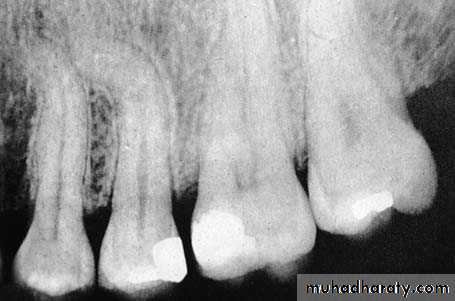

3- Extraction of Deciduous Molar that Embraces Crown of Permanent Tooth

Deciduous molar, whose roots embrace the crown of the succedaneous premolar

Envelope flap created and bone removed as far as the root bifurcationRoots of the molar sectioned with a perpendicular groove on the crown, which extends as far as the bifurcation

Removal of the distal portion of the tooth, which includes the crown and root, using forceps

Removal of the mesial portion of the tooth, which includes the crown and root

Suturing of the flap with interrupted sutures